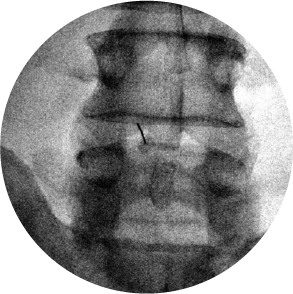

Incisión

El médico o el personal de enfermería realizan una pequeña incisión en la piel, después coloca una aguja hueca a través del hueso hasta alcanzar la médula ósea.

Extracción

Con una jeringa colocada en la aguja, se extrae una muestra de la porción líquida de la médula ósea. Podrías sentir un pinchazo o dolor breve y punzante. La aspiración solo tarda unos pocos minutos. Se pueden tomar varias muestras.

Muestra de médula ósea

El médico o personal de enfermería utiliza una aguja más grande para obtener una muestra de tejido de médula ósea sólida. La aguja para biopsia tiene un diseño especial para extraer un cilindro tisular (muestra cilíndrica) de médula ósea.